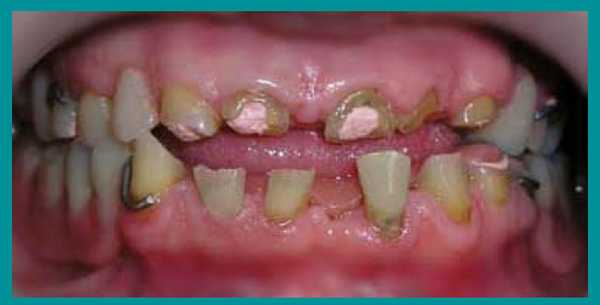

Трудности с пережевыванием пищи, отсутствие зубов, недовольство своим внешним видом, невозможностью улыбаться окружающим - вот неполный перечень тех жалоб, с которыми пациентка обратилась за стоматологической помощью. Из опроса выяснилось, что из-за страха перед лечением визит к стоматологу откладывался надолго, а точнее - на 31 год…

Осмотр выявил очень сильную горизонтальную стираемость верхних и нижних зубов, снижение высоты прикуса и изменение его из нормального в обратный (нижние зубы при смыкании находились впереди верхних). Одновременно на ортопантомограмме височно-нижнечелюстного сустава определялся двухсторонний подвывих нижней челюсти.

После осмотра и рентгенологического обследования зубочелюстной системы был предложен следующий план лечения:

- постепенное поднятие высоты прикуса при помощи протезирования,

- эндодонтическое лечение и подготовка оставшихся зубов к использованию в протезировании,

- изготовление культевых вкладок для создания коронковой части опорных зубов,

- переведение достигнутого центрального соотношения челюстей в центральную окклюзию, т.е. протезирование несъемными металлокерамическими коронками и частично-съемными бюгельными протезами.

Пациент был предупрежден о длительности лечения - оно должно занять не менее одного года. После расчета и моделирования ситуации на диагностических моделях и получения согласия пациента приступили к выполнению составленного плана лечения.